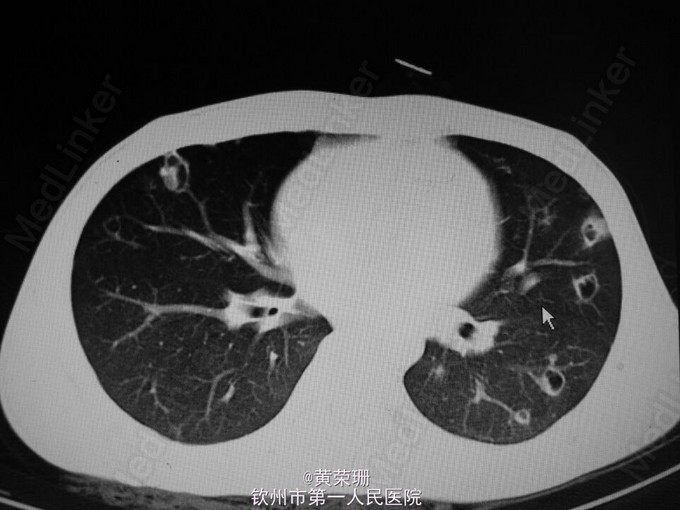

21岁青年男性患者, 急性起病,既往有静脉注射毒品史1月余。因“反复畏寒、发热20余天”入院。自诉20余天前以白开水化“毒品”静脉注射后出现畏寒、发热,体温最高达39.5℃,伴头部胀痛,浑身乏力,伴气促,活动后明显,伴咳嗽、咳痰,间中伴暗红色血丝痰,伴呕吐,为胃内容物,无明显腹痛、腹胀等。于当地门诊予“退热针”治疗后可退热,但易反复,15天出现双下肢几颜面部浮肿,于当地医院住院治疗,检查提示:WBC 25.4*10^9/L,Hb 58.2g/L,痰培养提示:金黄色葡萄球菌,伴少量白色念珠菌伴随生长。心脏B超:三尖瓣脱垂并关闭不全,治疗上余抗感染、输血、利尿等对症处理,但仍间中发热,遂至我院。 入院查体:心率112次/分,贫血貌,两肺呼吸音粗,双肺可闻及湿啰音,心界不大,心率112次/分,率齐,心音有力,三尖瓣听诊区可闻及3/6级收缩期吹风样杂音。 辅助检查:心脏B超:1.三尖瓣前叶赘生物(感染性心内膜炎),伴瓣口反流(重度)及前瓣穿孔,右房增大;2.左心室收缩功能测量值正常范围(图1)。胸部CT:1.考虑两肺感染(真菌感染?细菌感染?),2.两侧胸膜轻度增厚(图2-4)。入院后反复血培养、痰培养均未见培养出细菌几真菌。 主要诊断:1.感染性心内膜炎 三尖瓣赘生物并穿孔 三尖瓣重度关闭不全 2.肺部感染 患者入院后“哌拉西林他唑巴坦+阿米卡星”抗感染、强心、利尿、营养心肌等处理病情平稳后行三尖瓣置换术。术后病理:(三尖瓣)镜下见纤维性瓣膜局部增厚伴大量急慢性炎性细胞浸润,可见小脓肿形成,切表面有红染纤维素样炎性渗出物附着,结合临床符合感染性心内膜炎改变(图5)。